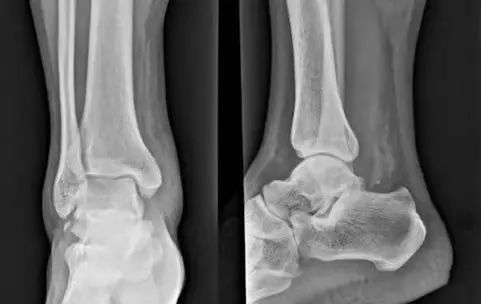

生活中,崴脚后常常忽视外固定的作用,特别是未存在撕脱骨折以及 X 线片假阳性者,踝关节应力位 X 片对于单纯的韧带损伤可发现踝关节不稳。

距骨倾斜角:内翻应力正位片中距骨相对于胫骨远端关节面倾斜角度 ≥ 9°,即可考虑踝关节不稳,但此时应考虑患者的职业,如芭蕾舞演员可存在足踝部韧带松弛

两则病例

28 岁青年女性,约 2 年前左踝首次发生崴脚,未行外固定处理,近 1 年来左踝间断多次崴脚,双侧踝关节应力正位片测量距骨倾斜角,左侧为 10°,右侧 4°,左侧应力位状态下感疼痛,右侧无不适感,考虑左侧踝关节不稳。

30 岁青年女性,1 年前右踝首次发生崴脚,未行外固定,伤后右踝间断数次崴脚,双侧踝关节应力正位片测量距骨倾斜角,左侧为 0°,右侧 7°,右侧虽尚不能诊断踝关节不稳,但距骨倾斜角增大,对比对侧仍考虑为崴脚后未外固定所致。